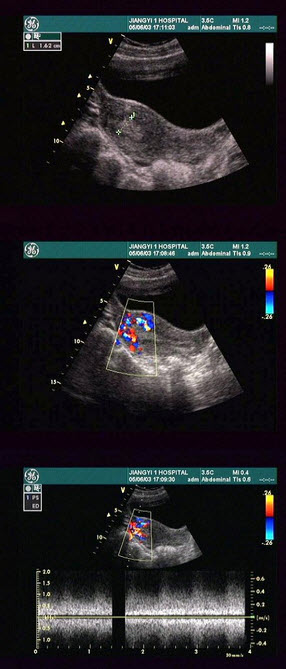

15、单项选择题

某患者,男,45岁,肝区不适,肝功能异常。行超声检查如图,诊断为()

A.弥漫性肝癌

B.结节状肝硬化

C.多发性血管瘤

D.血吸虫肝

E.不均匀性脂肪肝